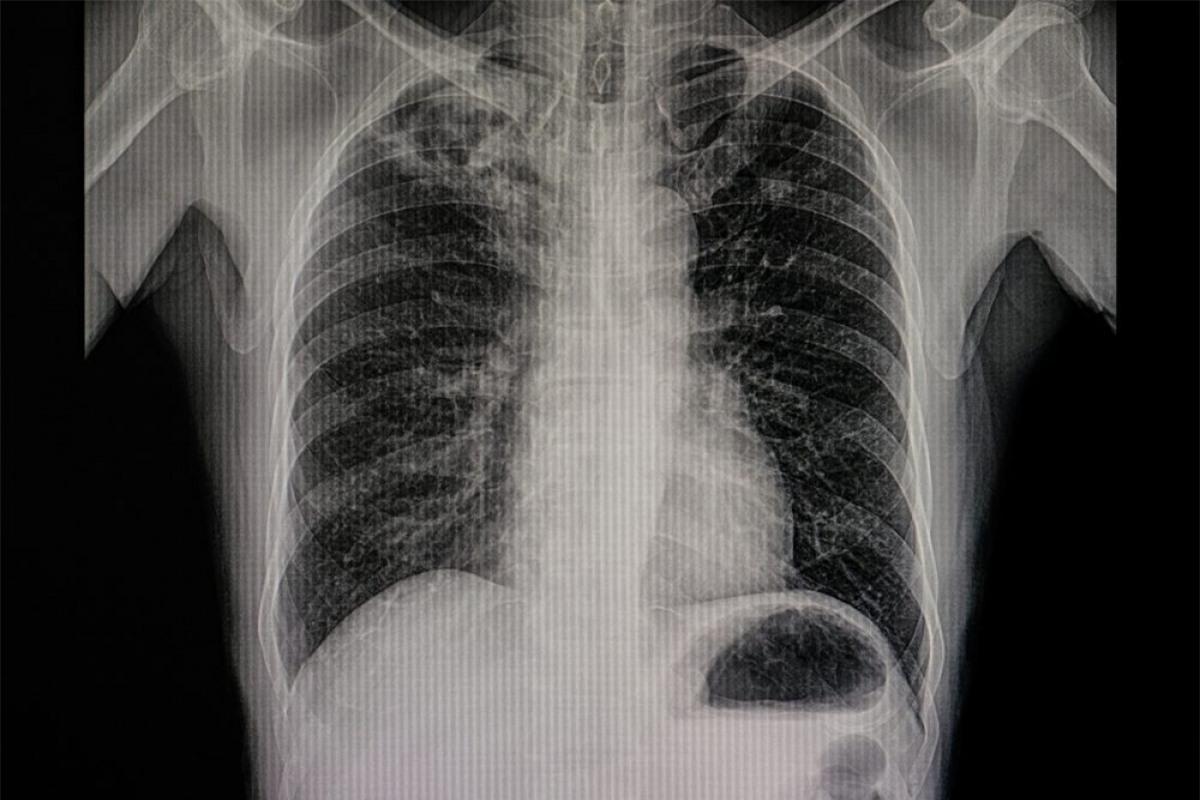

Phổi tắc nghẽn mãn tính: Đứng thứ ba trong các nguyên nhân gây tử vong trên thế giới là bệnh phổi tắc nghẽn mãn tính, hay COPD. Triệu chứng phổ biến của bệnh COPD bao gồm khó thở, thở gấp, thở khò khè và ho kéo dài.

Nhiễm trùng đường hô hấp dưới: Nhiễm trùng đường hô hấp dưới cũng là một trong những “thủ phạm” gây ra vô số ca tử vong mỗi năm. Dạng nhiễm trùng đường hô hấp dưới thường gặp nhất là viêm phổi. Nhiễm trùng đường hô hấp dưới được xem là bệnh lây nhiễm nguy hiểm nhất thế giới.

Ung thư hô hấp: Ung thư khí quản, ung thư phế quản và ung thư phổi gây ra 1,7 triệu ca tử vong trên thế giới vào năm 2016. Mặc dù các bệnh này thường gặp ở người hút thuốc lá, những người không hút thuốc cũng có nguy cơ bị ung thư hô hấp do khói thuốc hoặc ô nhiễm không khí.

Lao phổi: Bệnh lao phổi ảnh hưởng nghiêm trọng nhất đến phổi, nhưng nó cũng có thể tổn thương các bộ phận cơ thể khác như não bộ, da và ổ bụng. Bệnh lao phổi đặc biệt khó chữa, nhất là ở các quốc gia với cơ sở vật chất y tế chưa phát triển, do đó đây là một trong những nguyên nhân gây tử vong hàng đầu trên thế giới.